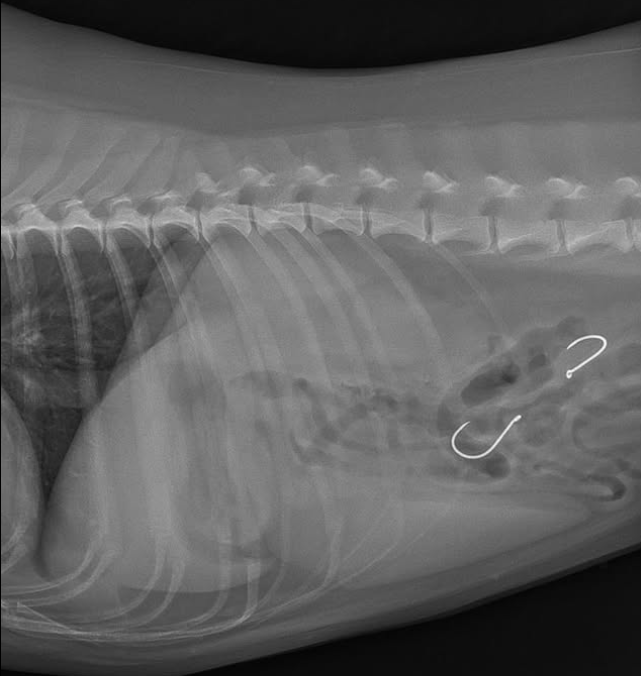

One vet shared an X-ray of a recent dog who had to have a hook removed from their stomach.

Speaking to @Marbellasequeja, they said: ‘I’m a veterinarian at a hospital in Mijas, and every day we see cases of dogs eating fishhooks on the beach, with a much higher incidence over the past month.

‘Most are fine; the hooks are removed endoscopically without incident. But others become complicated, requiring surgery, or the hooks are lodged in difficult places, which can even be fatal.